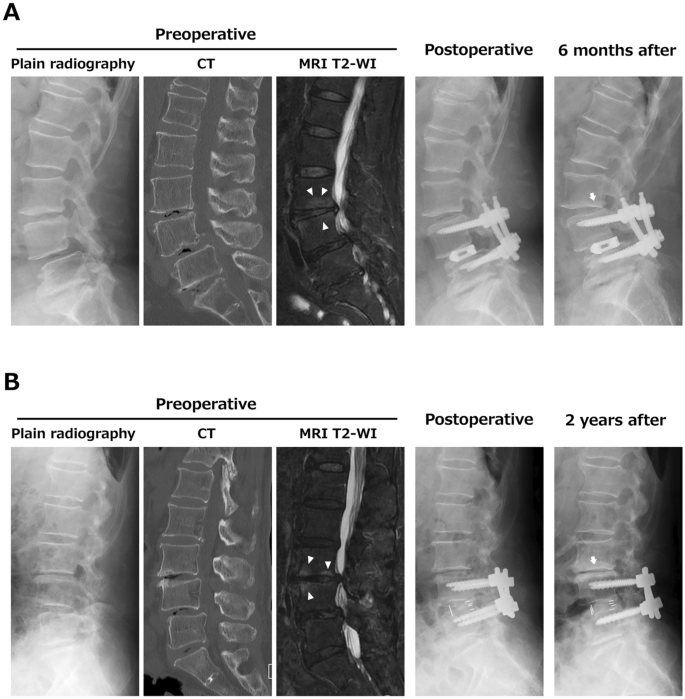

A 63-year-old female underwent PLIF at L4-5 with split laminotomy at L3-4. Preoperative CT and MRI indicated a vacuum phenomenon at L3-4 and L4-5, and bone marrow edema at L3-4. Preoperative % slip was 24%, Δ% slip was 3%, and disc space distraction was 2.4 mm. At 6 months after surgery, a decrease in disc height of > 3 mm was detected (Fig. 2A).

Representative cases. (A) A 63-year-old female with a preoperative vacuum phenomenon and vertebral bone marrow edema (arrowheads) at the caudal adjacent segment. At 6 months after surgery, there was a decrease in disc height. (B) An 82-year-old female with a preoperative vacuum phenomenon and vertebral bone marrow edema at the caudal adjacent segment (arrowheads). Surgical disc space distraction was 4.0 mm. At 2 years after surgery, the patient had a decrease in disc height with low back pain.

An 82-year-old female underwent PLIF at L4-5 with conventional laminotomy at L3-4. Preoperative CT and MRI showed a vacuum phenomenon at L3-4, L4-5 and L5-S1 and bone marrow edema at L3-4. Preoperative % slip was 18%, Δ% slip was 13%, and disc space distraction was 4 mm. At 2 years after surgery, the patient had a decrease in disc height of > 3 mm with low back pain (Fig. 2B).